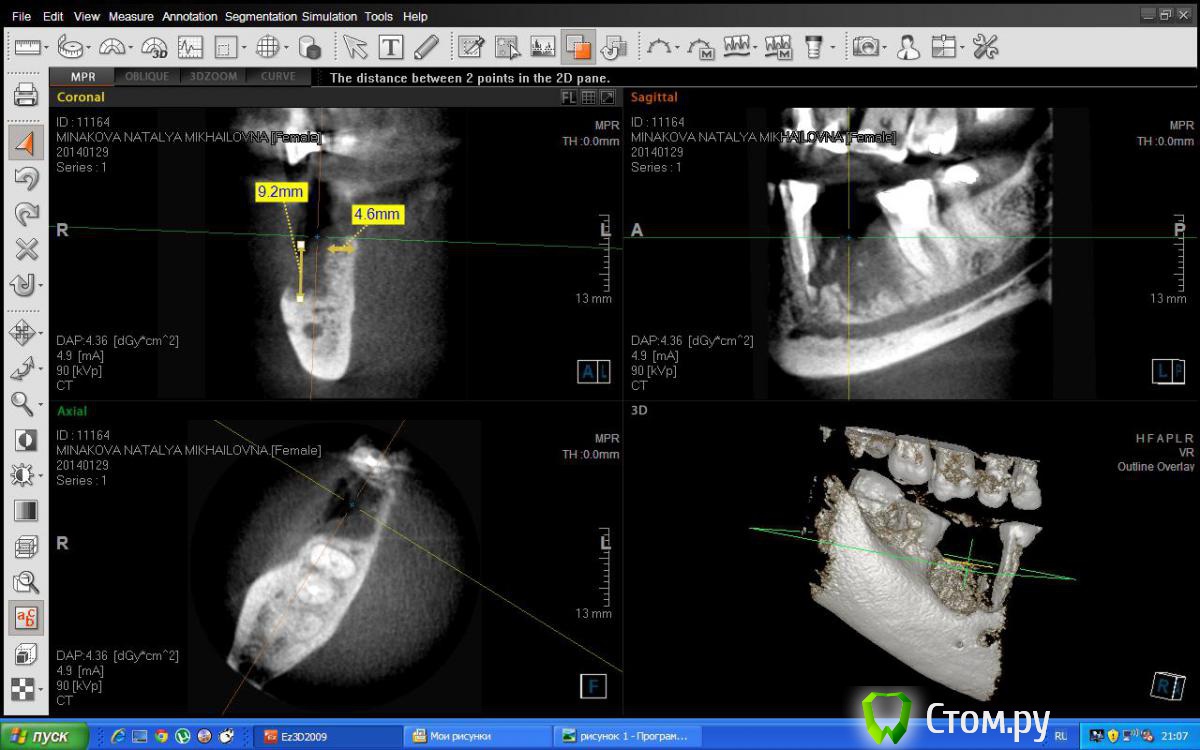

Татьяна Андреевна Опубликовано 15 мая, 2014 Поделиться Опубликовано 15 мая, 2014 Коллеги, заранее всем спасибо за ответы! очень,по-моему, интересный случай. Обратилась ко мне пациентка несколько месяцев назад с проблемой после резекции корня 46 зуба. Зуб уже почти весь плавал в остатках кости, все это нагноилось ,поэтому я не особо стала разбираться зачем здесь была резекция. Я удалила зуб. направила на кт черезе 3 месяца.И вот результат. Сохранилась только язычная стенка. ну во время удаления там уже был огромный кратер,поэтому я не особо удивилась. Решила посоветоваться с вами,боюсь неправильно сделать костную пластику, тк 45 зуб уже тоже оставляет желать лучшего(увидела уже это на кт). Вопросы как бы вы восстанавливали такой костный дефект(ламинаты или блок или сетка ), мягкие ткани и что бы сделали с 45 зубом. ?? Ссылка на комментарий

Татьяна Андреевна Опубликовано 16 мая, 2014 Автор Поделиться Опубликовано 16 мая, 2014 (изменено) Соглсен, высота есть, а это уже хорошо, такой дефект можно любым из перечисленных способов закрыть, сеткой или цитопластом мне кажется предсказуемей будет результат чем ляминой, так же и с ламинатом будет, только ауто поищите откуда забрать. А по поводу 45, можно еще пару срезов?вот такой срез например Изменено 16 мая, 2014 пользователем Татьяна Андреевна Ссылка на комментарий

Bier Опубликовано 16 мая, 2014 Поделиться Опубликовано 16 мая, 2014 Если это не артефакт и корень пятерки действительно так резорбирован, то удаляйте. Через пару мес можно аугментировать все 1 Ссылка на комментарий

Alexey Doc Опубликовано 16 мая, 2014 Поделиться Опубликовано 16 мая, 2014 (изменено) Какими видами аугментаций вы владеете?По этим срезам и 4.7 зуб в долгосрочном прогнозе тоже под сомнением, область бифуркации истончена и МЯ канал пуст. Изменено 16 мая, 2014 пользователем Alexey Doc Ссылка на комментарий